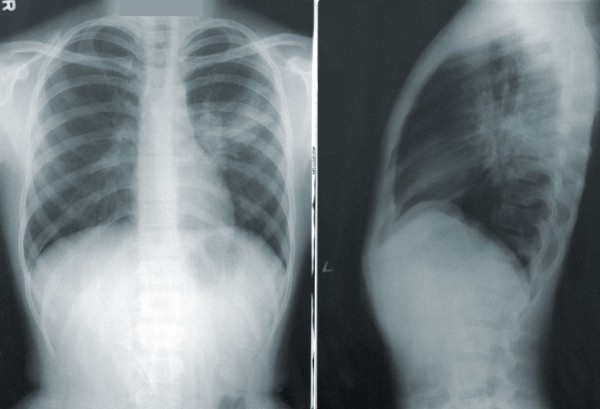

На девятый день мне лучше не стало, звоню врачу, сообщаю об этом. Она советует вызывать скорую помощь, что я и сделала. Машина приехала примерно через 4 часа. Пока ждали, я сходила в платную клинику на КТ за 4,5 тыс. рублей. При записи выяснилось, что там, где более гуманные цены, очередь до двух-трех недель вперед. Коммерческую клинику не волновало, есть ли у меня температура и другие симптомы. Выписка из КТ: «Очаги матового стекла справа внизу, область поражения КТ-1 (<25%), пневмония, вероятность COVID-19 высокая».

Когда проснулся в этот день, решил, что мне обязательно нужно сделать КТ. Но с этим возникли трудности, поскольку в одной клинике ближайшая запись была через два дня, в других — еще позже. Я позвонил в клинику, где сдавал тест на коронавирус. Мне сказали, что, поскольку он положительный, нужно ждать, когда его подтвердит Роспотребнадзор. Я уточнил, могу ли пройти КТ. Ответили, что могу попытаться, но не у них точно. В итоге я нашел, где его пройти, притом что у меня не было на руках бумаг с положительным тестом. Я обзвонил много клиник, мне отказали. Потом вспомнил, что КТ есть в Славянске-на-Кубани. Я записался и сделал томографию в тот же день. КТ показала чистые легкие, но курс из двух антибиотиков, которые принимают при ковиде, я уже начал.

Платные клиники не имеют права ни брать анализы на коронавирус, ни делать КТ людям с признаками ОРВИ. Но, если температура ниже 37,4, все окей. В клинике, куда мы обратились, позабавил тот факт, что при оплате КТ получаешь скидку 30% на тест на COVID-19. Воспользовались акцией и все сдали. КТ показала, что в текущий момент активного очага инфекции нет, но есть фиброзные спайки. Я созвонилась с несколькими врачами, их мнения на этот счет разделились. Одни сказали, что так и прошла молнией ковидная пневмония у Алисы. Другие специалисты утверждали, что это дело минувших болезней. Мне посоветовали взять путевку в бальнеолечебницу и полечить дыхательную систему, когда ребенок поправится.

Спустя две недели после первых симптомов у дочки мне стало плохо: головная боль и боль в горле, кашель, температура 37, задыхаюсь. В 18:45 понимаю, что нужно скорую вызывать. Оператор сразу предупредил: «Наберитесь терпения, нереально много вызовов, скорая приедет через 10—12 часов». После того как поняла, что машина будет не раньше утра, отправилась в платную клинику, сделала КТ и уже получила результат — поражение легких до 25% — к моменту приезда скорой в 9:30.

На следующий день мы снова вызвали скорую помощь: мне стало плохо, я начала задыхаться. К этому времени мы уже пили различные противовирусные препараты. Когда машина приехала, результата теста мужа еще не было на руках. Мы описали симптомы, сообщили, что болеем почти неделю. Врач ответил, что не может назначить нам лечение, нужно связываться с больницей. Вечером того же дня мне стало очень плохо, мы пошли делать компьютерную томографию. Как выяснилось, у меня было поражено 16% легких, у супруга — 20. В результатах было указано, что высока вероятность коронавирусной инфекции.

Через день с нами связалась участковый врач, уточнила, как мы лечимся, как протекает заболевание. Ночью я начала задыхаться. Снова вызвали скорую помощь, я сказала, что у мужа положительный тест на COVID-19, мне плохо, есть результаты КТ. Врач ответил, что нам требуется госпитализация. На следующий день утром мы пошли делать повторную компьютерную томографию. Результат показал, что площадь поражения стала еще больше.